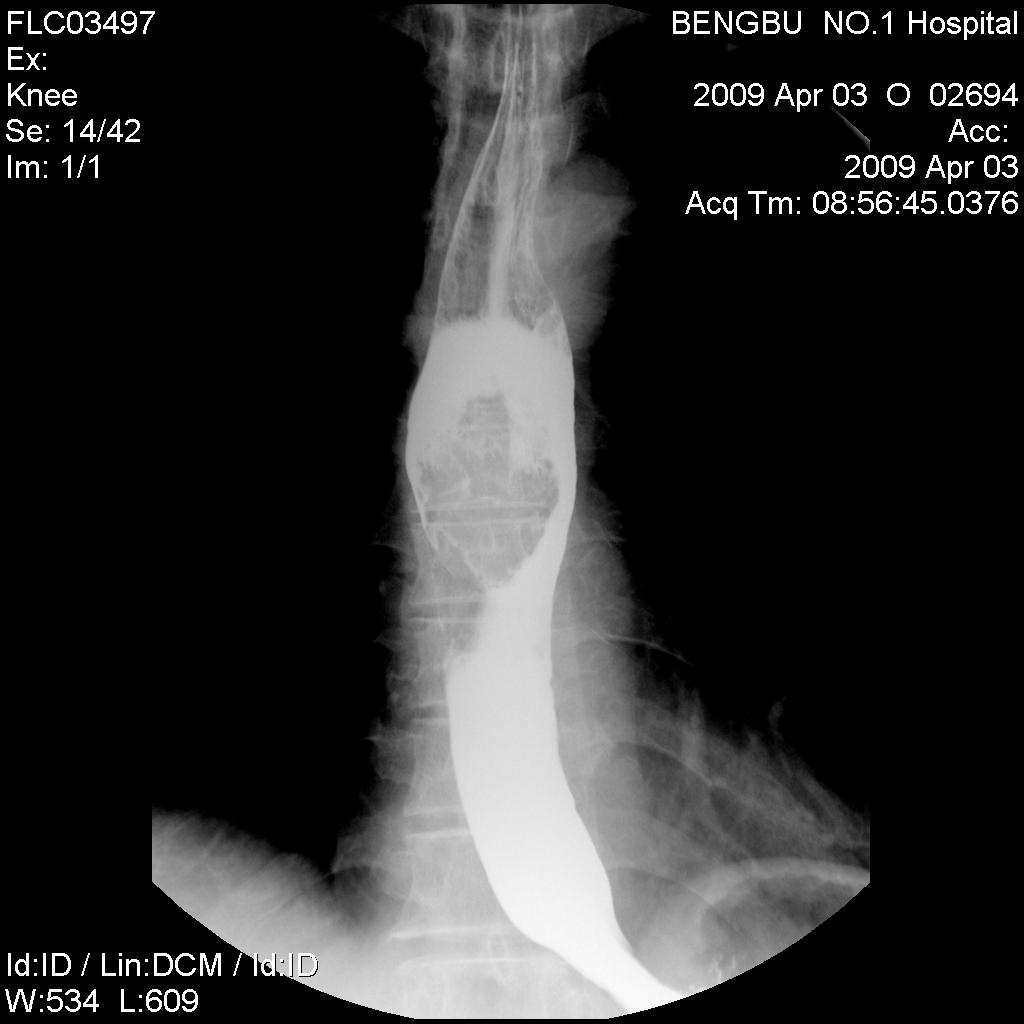

标题: X5565:男,50岁,吞咽阻塞感1月余。 [打印本页]

标题: X5565:男,50岁,吞咽阻塞感1月余。

食管中下段椭圆形充盈缺损,钡剂呈分流尚通畅,粘膜未见明显中断,其上段未扩张。初步考虑食管平滑肌瘤。曾有一病例影像表现类同,结果似为未分化癌。

食管中下段椭圆形充盈缺损,钡剂呈分流尚通畅,粘膜未见明显中断,其上段未扩张。初步考虑食管平滑肌瘤。

食管中下段椭圆形充盈缺损,边缘尚光滑,钡剂呈分流状通过块影,粘膜未见明显中断,管壁未见明显僵硬和缩窄改变。-----平滑肌瘤可能性大。

诊断:食管中下段椭圆形充盈缺损,边缘清晰光滑,肿块表面钡剂涂布征,似见细小龛影,钡剂分流改变,患段官腔扩张度及柔软度尚好,无明显僵硬及狭窄,上段以上食管未见明显扩张及钡剂储留,考虑食管平滑肌瘤,未除外溃疡性食道癌,建议食管镜活检。

肿块呈腔内膨胀性生长,边缘光滑

结果:食道癌。